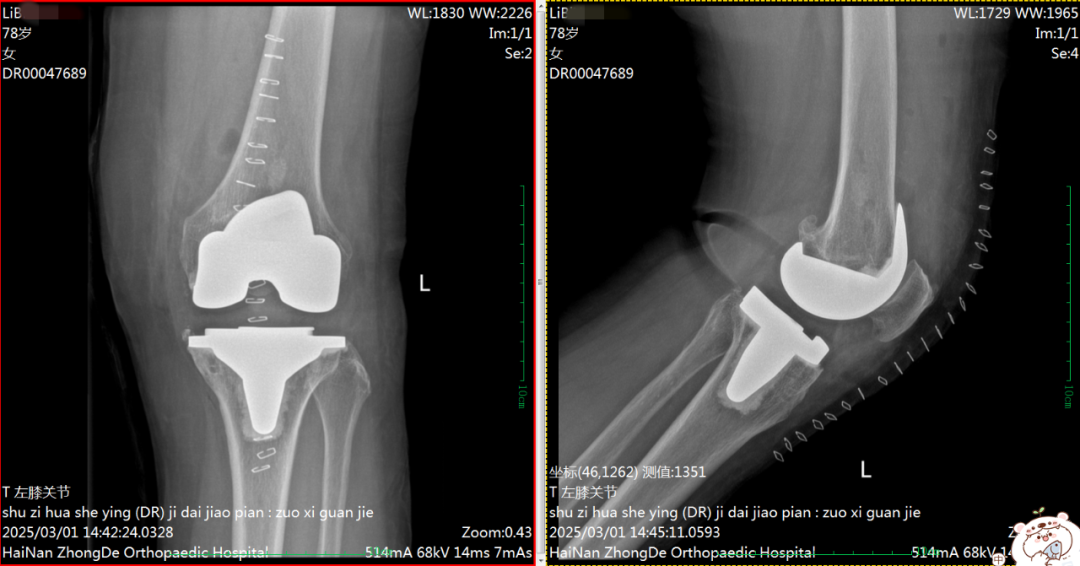

膝内翻(O型腿)术前术后对比

术前DR片

术后DR片